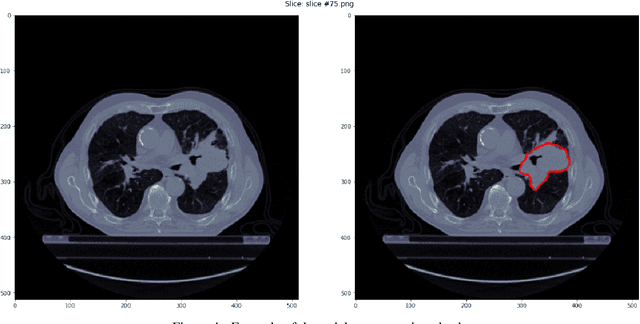

Medical image analysis plays a key role in precision medicine as it allows the clinicians to identify anatomical abnormalities and it is routinely used in clinical assessment. Data curation and pre-processing of medical images are critical steps in the quantitative medical image analysis that can have a significant impact on the resulting model performance. In this paper, we introduce a precision-medicine-toolbox that allows researchers to perform data curation, image pre-processing and handcrafted radiomics extraction (via Pyradiomics) and feature exploration tasks with Python. With this open-source solution, we aim to address the data preparation and exploration problem, bridge the gap between the currently existing packages, and improve the reproducibility of quantitative medical imaging research.